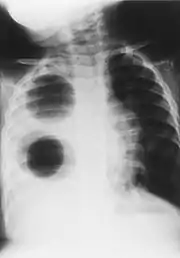

Pulmonary agenesis

Chest radiograph of a woman with unilateral pulmonary agenesis

• Chest X-ray is effective in detecting the traits of lung herniation.[1] The unaffected side of lung tends to undergo hypertrophy, and move towards the empty space in the chest wall on the opposite side.[1] This herniation could be indicated by fluoroscopy.[1] With age increasing, the herniation progresses and ease its detection.[1]